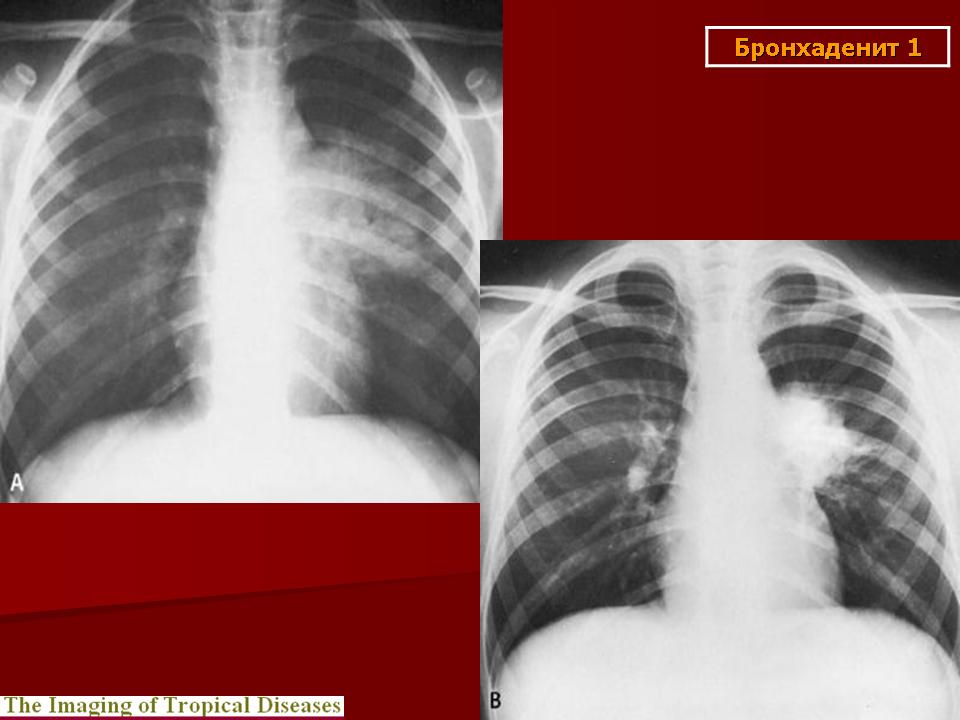

Различают инфильтративный, опухолевидный и малые формы туберкулеза внутригрудных лимфатических узлов. Опухолевидная форма проявляется увеличением размеров лимфатических узлов в результате воспалительной гиперплазии, что обнаруживается при рентгенологическом исследовании. Контуры лимфатических узлов на рентгенограмме и томограммах четкие. Инфильтративный туберкулез внутригрудных лимфатических узлов характеризуется не только увеличением узлов, но и развитием инфильтративных изменений в легочной ткани, в прикорневых ее отделах. Малые формы проявляются незначительным увеличением внутригрудных лимфатических узлов, что выявляется главным образом на томограммах с поперечным размазыванием в прямой или боковой проекциях. Этот вариант заболевания в последнее время встречается чаще, чем в прежние годы.

Томографические симптомы (признаки) туберкулезного бронхоаденита